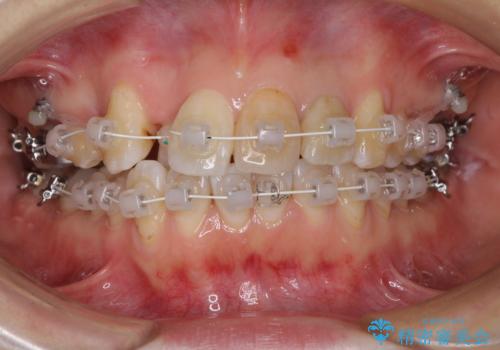

- 審美装置

- 1年7ヶ月

- 10-30回

内側に転位していた歯はきれいに歯列に収まり、清掃性が著しく改善しました。

元々神経の失活してしまっている前歯2本は変色が目立つようになってきたため、今後セラミッククラウンによる補綴治療を行う予定です。